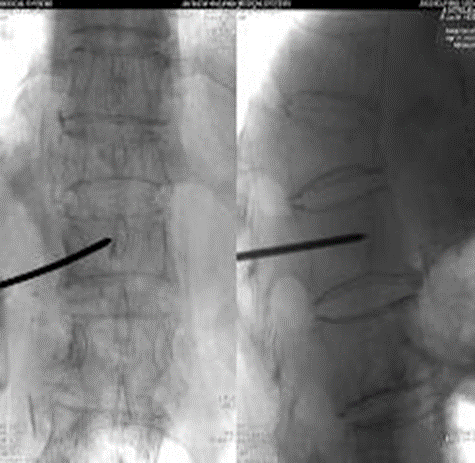

椎体定位:正侧位脊柱呈标准正位:左右两侧椎弓根投影对称,棘突投影位于椎体正中央进针点:椎弓根外侧缘中点略偏足侧的体表投影向外旁开1.5-2cm。进针方向:向矢状面成10°-15°

侧位:针尖至椎弓根的1/2;正位:针尖位于椎弓根影的中线处侧位:针尖至椎体后缘;正位:针尖位于椎弓根的内侧缘侧位:针尖至椎体前中1/3交界处;正位:针尖位于椎体中线略偏对侧

骨钻建立通道:钻头尖到达椎体前1/3处钻动骨钻时可闻及钻动骨质的沙沙声用带芯的骨水泥填充器探测,证实椎体前缘皮质未破

放入可扩张球囊,确保球囊位于椎体内(扩张前透视)扩张球囊:先加入2ml左右造影剂,同时时观察压力表,后每次增加造影剂0.5ml,透视至椎体扩张到满意程度,球囊系统压力控制在15个大气压左右。

注意:扩张球囊时对侧骨钻要抽出

球囊停止加压:A.终板抬高,达到治疗时B.球囊靠近骨皮质或终板时C.对比剂已注入4MLD.扩张压力已达到15个大气压左右